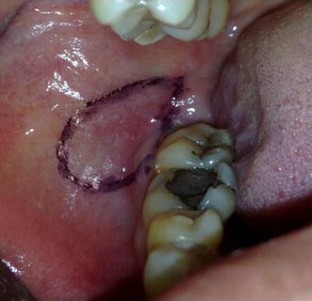

Fig. 1

Fig. 2